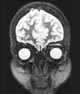

Primary orbital neoplasm

Eye neoplasms can affect all parts of the eye, and can be a benign tumor or a malignant tumor (cancer). Eye cancers can be primary (starts within the eye) or metastatic cancer (spread to the eye from another organ). [Source: Wikipedia ]